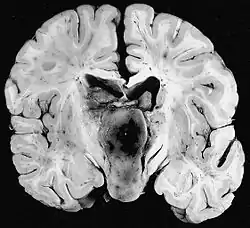

Anatomía patológica

Macroscópicamente, el astrocitoma pilocítico suele presentarse como una masa quística bien definida, con un nódulo mural en la pared del quiste. Si es sólido, puede estar bien circunscrito o, con menos frecuencia, ser infiltrativo.

Microscópicamente, el tumor muestra un patrón bifásico, con células bipolares compactas de forma pilosa (de ahí su denominación "pilocítico") con largos procesos positivos para GFAP y zonas hipocelulares con microquistes. En las zonas sólidas, la neoplasia se compone de astrocitos neoplásicos con un citoplasma fibrilar intensamente eosinofílico y núcleos alargados y redondeados sin atipias. En las zonas microquísticas las prolongaciones citoplasmáticas tienen siempre la apariencia de fibrillas pero son menores en número y se irradian en todas direcciones. Son muy frecuentes en el astrocitoma pilocítico las fibras de Rosenthal[3][7] y los cuerpos granulares eosinofílicos. También puede haber proliferación vascular de aspecto glomeruloide no indicativa de malignidad.